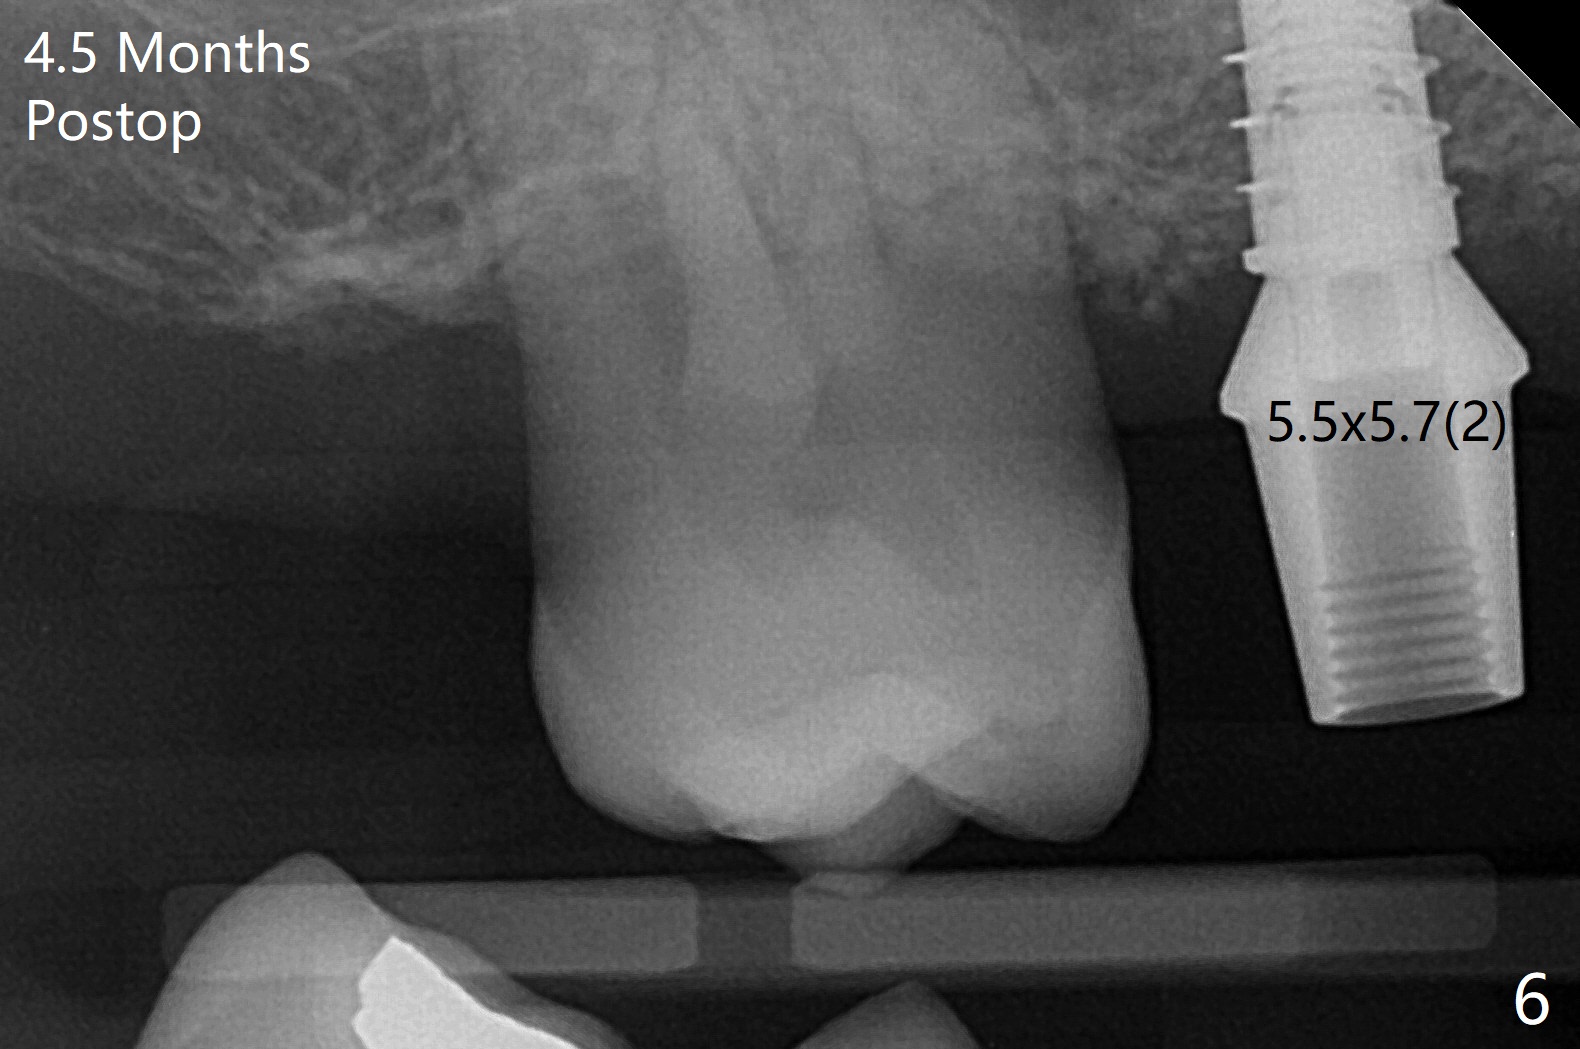

49岁女(个子小)牙齿问题多,同意先做右上5,6种植,6骨质高度1-2毫米,一个月前因动脉出血外提升失败。今天她回来做内提升,同意如果条件合适,同期徒手植牙(将来做一个磨牙牙冠),事先服用阿奇霉素。使用粘性骨粉和报废植体做内提(图一:*),最后植入4x7毫米植体(35Ncm),近中颊侧平牙槽嵴(图二:*),其余骨上 (图三: *),不敢植入太深,怕掉入上颌窦。第二个预防掉入上颌窦措施是利用大号基台(图三),然后在基台周围放置骨粉(图四:*,五),缝合,牙周敷料。伤口愈合后,准备制作树脂敷料,防止植体和基台往口腔脱落。术后五天复诊,无上颌窦炎症,牙周敷料稳定。她再回来时已经术后4.5个月,植体稳定,更换基台没有疼痛(图六,七),口腔卫生极佳,使用水牙线,不敢患侧刷牙。